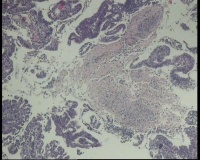

镜下见子宫内膜腺体异型增生,呈乳头状,筛网状排列,细胞核圆形,大小尚均匀,可见少量核分裂像,部分区域鳞化,间质少,部分区域无间质,间质有坏死

有些区域不能除外浆液性癌,最好做一做免疫组化协助鉴别。

浆液性癌!建议P53;P16'ER;PR等确认!